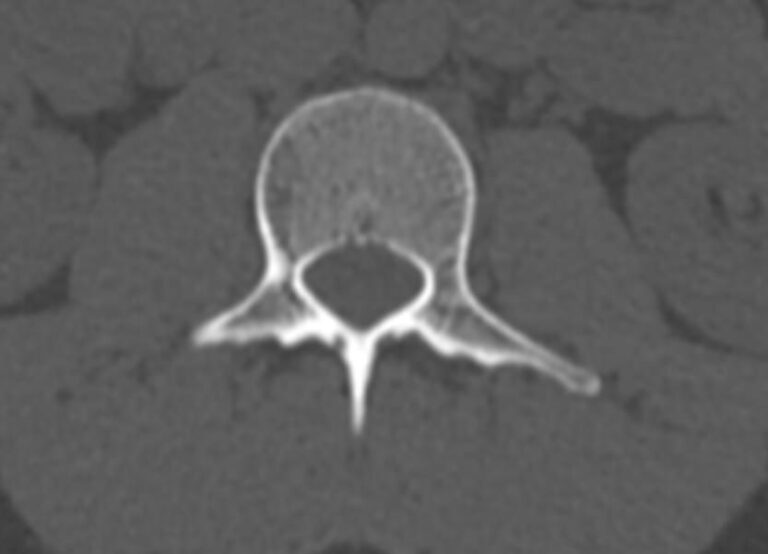

Мультиспиральная компьютерная томография является одним из наиболее информативных методов диагностики дегенеративно-дистрофических заболеваний, травматических, воспалительных изменений, а также опухолевых процессов позвоночника. Методика предусматривает использование рентгеновского излучения для получения детализированных снимков костных структур позвоночника, межпозвонковых суставов и межпозвоночных дисков.

С помощью мультиспиральной КТ можно диагностировать:

- дегенеративно-дистрофические заболевания позвоночника (остеоартроз, спондилез, деформирующий спондилоартроз);

- травматические повреждения позвоночника (компрессионные и оскольчатые переломы);

- стеноз (сужение) позвоночного канала;

- грыжи межпозвонковых дисков (протрузии, экструзии и грыжи Шморля);